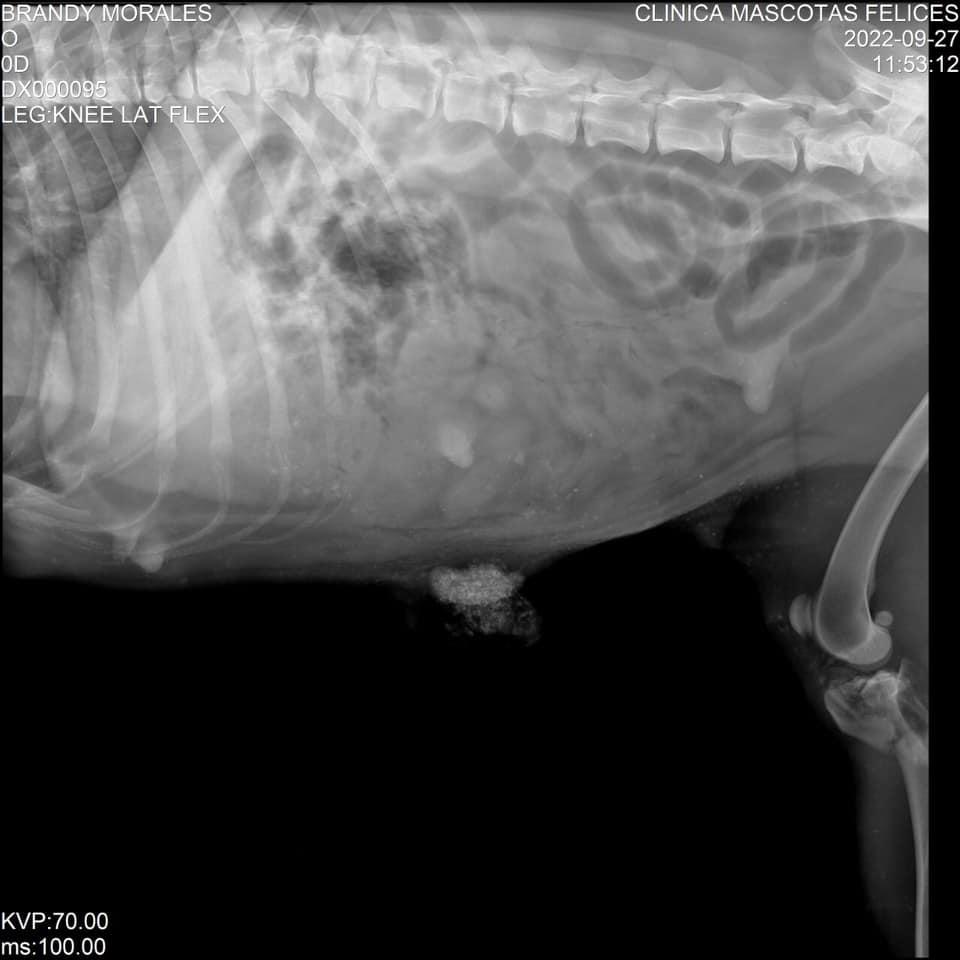

Radiografía de la perrita.

Brandy está interna en una clínica veterinaria. Los médicos le hicieron radiografías y confirmaron que una de sus patas fue fracturada.